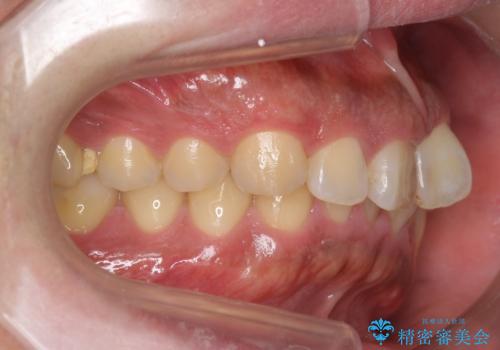

前歯のねじれを 1年かけずに矯正 インビザライン

- 前歯のねじれを主訴に来院。

インビザラインで治療しました。

前歯のねじれをセラミックで治そうとすると、抜髄といって、神経の治療が必要になる上、歯の幅も制限が出て理想的にはなりません。

保定の必要がありますが、天然歯を並べる矯正治療では、治療後の心配事が非常に少なく、保存的な処置となります。